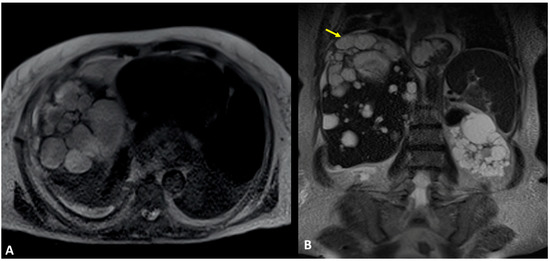

3.4. Case #4: Pancreaticopleural Fistula

4. Results and Discussion